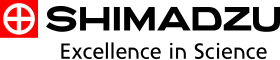

04 视金识功能

在断层融合技术的基础上SONIALVISION SMIT推出了视金识功能。该功能是针对金属假体周边的金属伪影而设计,可以有效的减少伪影的产生。在关节置换的术后评估,定期检查、翻修等起到了突破性的影像参考作用。